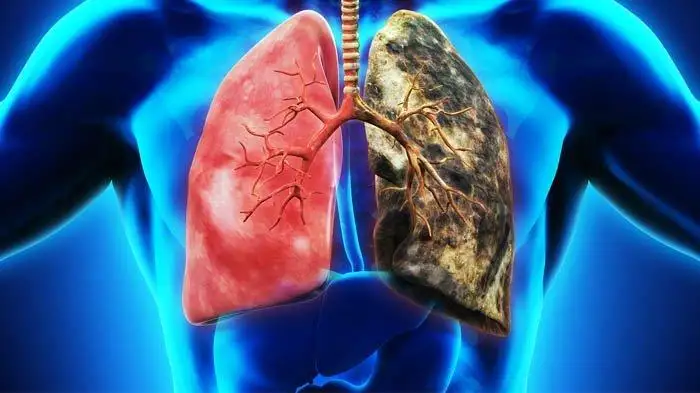

肺がんは世界的に死亡率の高いがんの一つであり、日本においても主要ながん死因の上位を占めています。特に近年は高齢化の進行や生活習慣の変化に伴い、発症数が増加傾向にあります。「肺がん 原因」を正しく理解することは、発症リスクの低減や早期発見につながる重要な第一歩です。喫煙との関連は広く知られていますが、実際にはそれ以外にも多様な要因が関与しています。…

肺がんは日本におけるがん死亡原因の上位を占める重大な疾患であり、その中でも肺がん ステージ 4は最も進行した段階を指します。ステージ4と診断されると、多くの患者さんやご家族が強い不安を感じますが、近年は医療の進歩により治療選択肢が大きく広がっています。分子標的治療薬や免疫チェックポイント阻害薬の登場により、従来よりも長期生存が期待できるケースも増えています。…